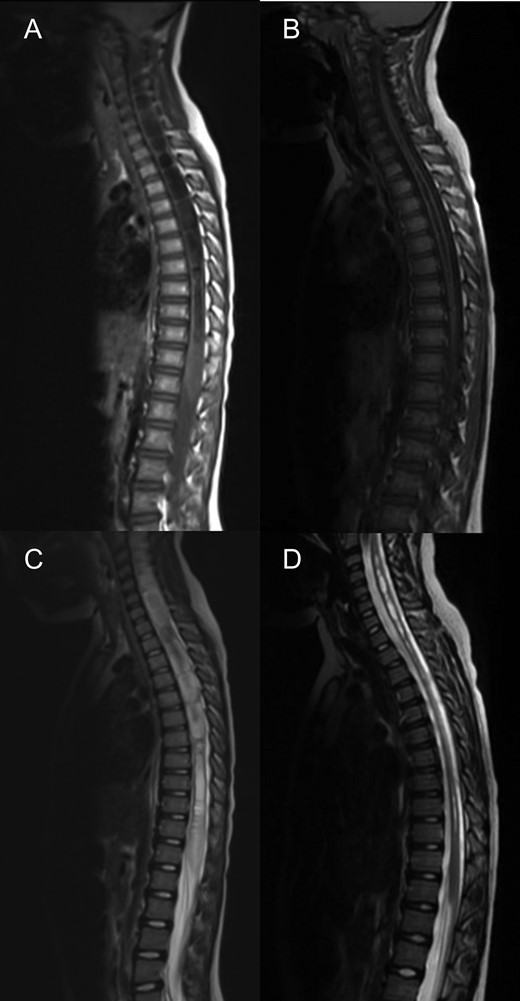

MRI spine sagittal sections demonstrating a holocord syrinx decreasing in size following surgery. Pre (A) and 3 years post op (B) T2. Pre (C) and 3 years post op (D) and T1.

At 1 year follow-up, his foot drop had gradually improved. He was able to walk on his tip toes and heels. By 2 years follow-up, his foot drop had completely resolved and ankle dorsiflexion was 5/5 on the right. An MRI at three years post op demonstrated a good foramen magnum decompression (Fig. 1) and significant improvements in the syrinx (Fig. 2), however not complete resolution.